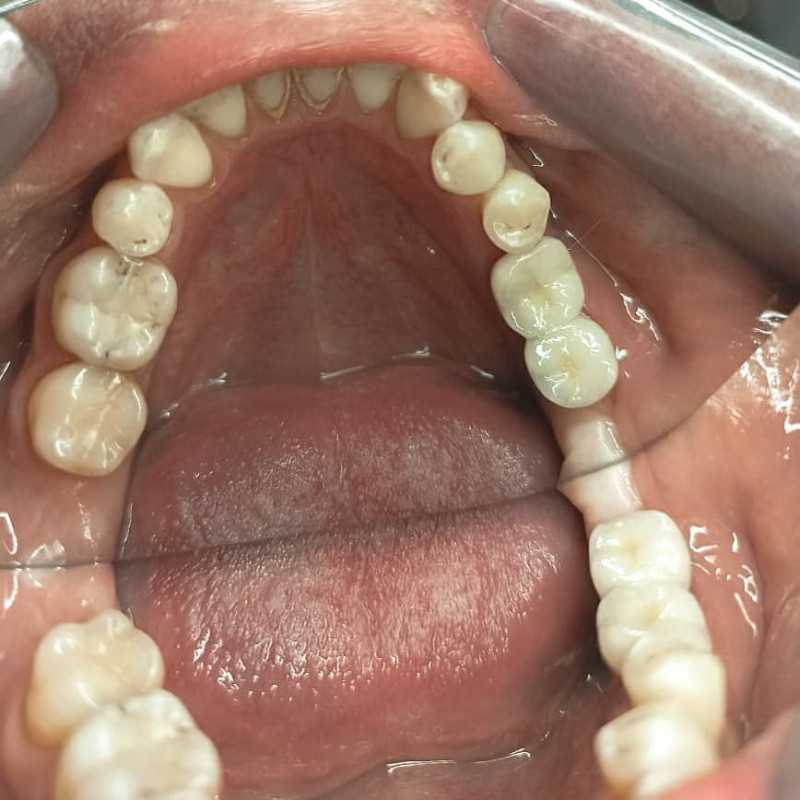

Тотальное протезирование верхней челюсти металлокерамическими коронками с опорой на имплантаты Astra-Tech (Швеция) с левой стороны, и на свои зубы с правой стороны